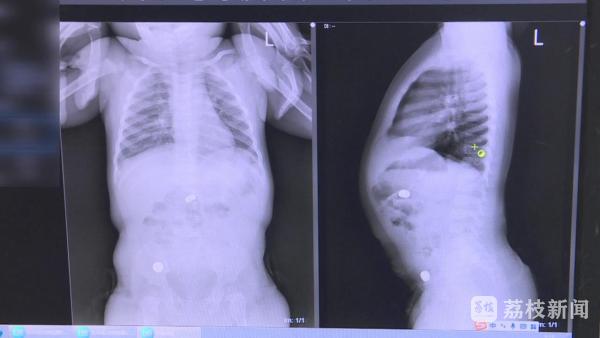

5月22日晚上11点多,淮安市妇幼保健院小儿外科医生通过急诊手术,从1岁男童小天的腹内取出两颗已经破损、泄漏的纽扣电池,小天肠壁已被电池溶液腐蚀发黑。

淮安市妇幼保健院小儿外科主治医师张岩说:“我们发现一颗纽扣电池位于十二指肠的地方,还有一颗位于距离回盲部十公分的回肠位置,两个地方都出现了发黑坏死的前期症状,如果再拖延的话就会出现消化道穿孔,我们取出电池也发现电池表面有少许破损泄漏的迹象。”